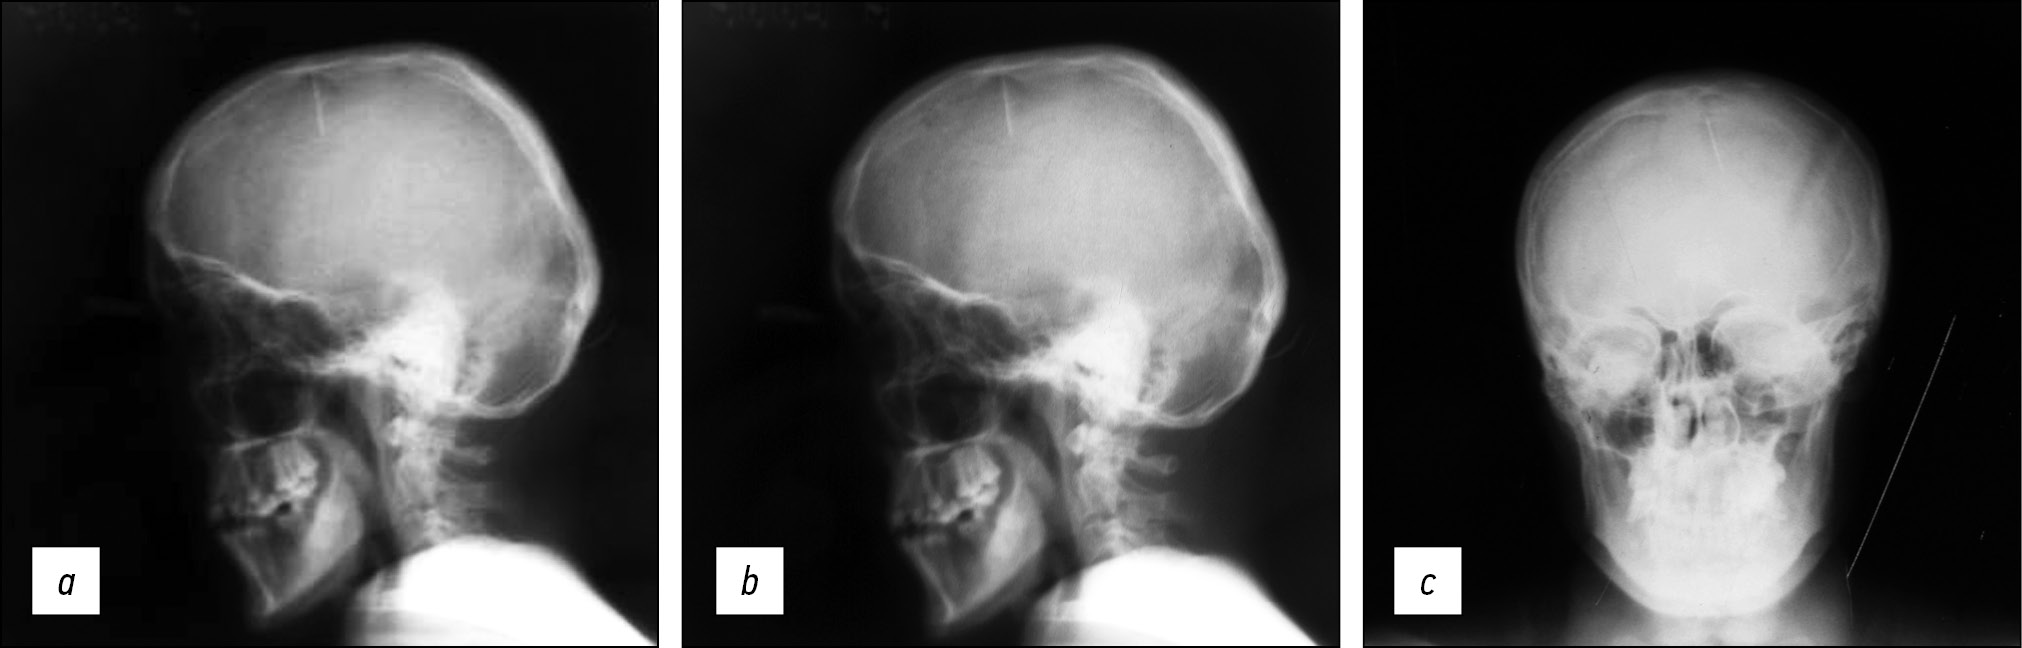

Fig. 1. Radiography in lateral (a, b) and direct (c) projections: Intracranial foreign metal body (sewing needle).

General analyses of the blood and urine, electrocardiography, and fluorography of thoracic organs were normal. Traumatic bone changes were not observed in the roentgenography of the right hand. Roentgenography of a skull: “One foreign body, a metal needle was found in the intracranial region.”

The patient (25 years old) was from the southern region of the republic. The patient, his family, and parents were unaware of the intracranial foreign metal body (sewing needle) until the examination. His parents could not give any anamnestic information about the existence of the sewing needle in the intracranial region. Nevertheless, according to the mother, it was alleged that the patient’s aunt harbored feelings of envy toward him from an early age, raising the possibility of her involvement in the incident. Clearly, a sewing needle can be entered into an intracranial region only until the sinciput becomes firm. As the needle tip was pointing down, the needle was considered intentionally pricked (Figures 1–3). The accident can be unambiguously evaluated as the result of an unsuccessful crime. Cases of pricking sewing needles into the sinciput to incapacitate babies and murder them are mostly reported in eastern countries (Turkey, Iran, and India) [22-25]. Following further examination, the patient was found to be the only grandson in the family, and near relatives enviously entered a sewing needle into his intracranial region from the sinciput to murder him while he was a baby. Fortunately, the foreign body did not injure the cerebral hemispheres and the front branch of the cerebral artery, not causing infection; therefore, clinical neurological symptoms and complications were not observed. However, psychopathic features were observed in the personality of the patient as he grew older.